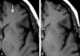

Diploic channel

The diploic veins are large, thin-walled valveless veins that channel in the diploĆ« between the inner and outer layers of the cortical bone in the skull. They are lined by a single layer of endothelium supported by elastic tissue. [Source: Wikipedia ]